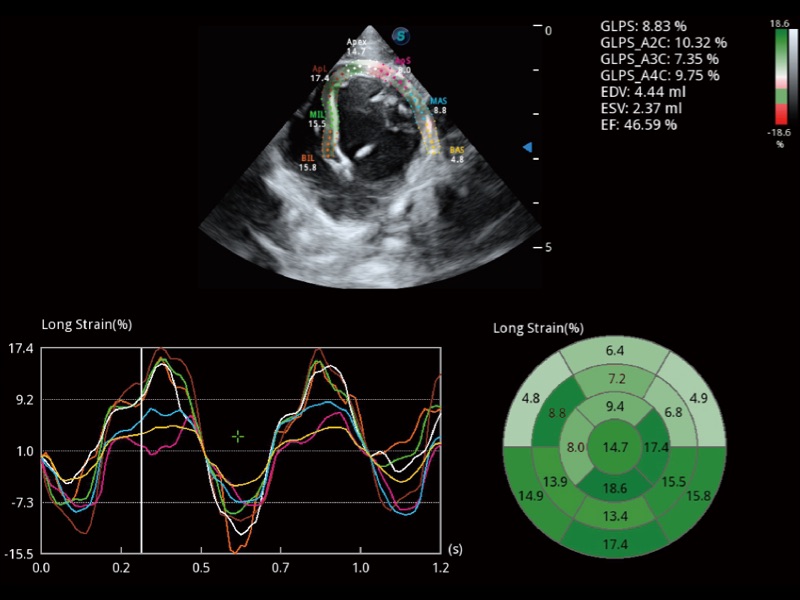

能夠基于左心室壁追蹤和辛普森法,自動計(jì)算射血分?jǐn)?shù),支持多個可移動點(diǎn)描跡,與手動測量相比,極大節(jié)省了動物醫(yī)生的時(shí)間和精力。

具備多種協(xié)議可選,同時(shí)支持17階段劃分法和專業(yè)的SE報(bào)告。

通過360度任意調(diào)節(jié)3條M型取樣線,在同一心動周期上觀察心臟不同位置的運(yùn)動曲線,得到準(zhǔn)確的心功能測量數(shù)據(jù),有效評估心肌運(yùn)動及左心室功能。

實(shí)時(shí)用顏色表示心肌組織運(yùn)動,觀察和定量組織的運(yùn)動情況,對快速檢測與評估心肌的灌注和活性、電傳導(dǎo)及心肌收縮和舒張功能等均能提供重要的診斷信息。